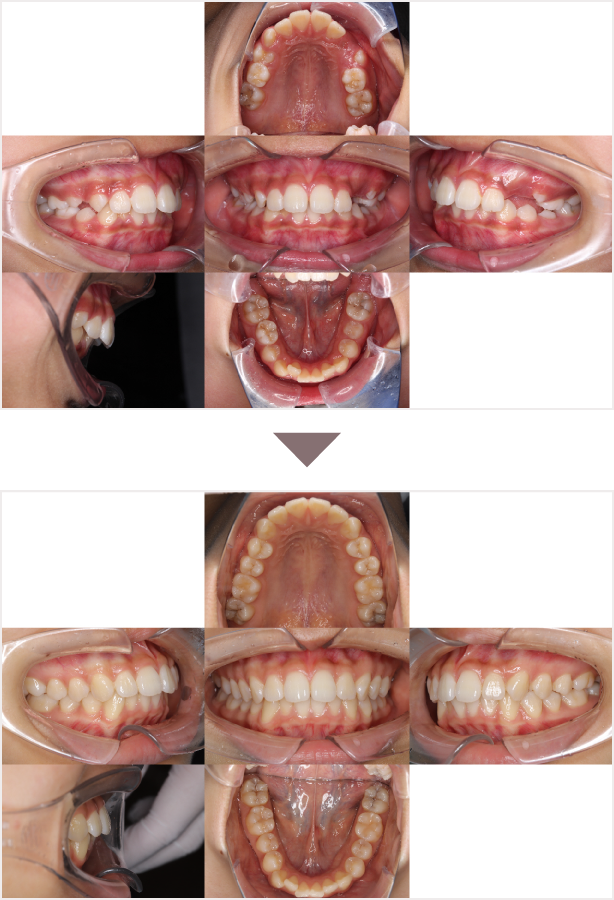

症例叢生

性別

期間7年7ヶ月

治療内容N-Bimler装置、Neo-Capを使用して治療

治療における

副作用・リスク

装着しないと効果は出ません

金額ビムラー装置:550,000円

ネオキャップ:4本

合計:572,000円